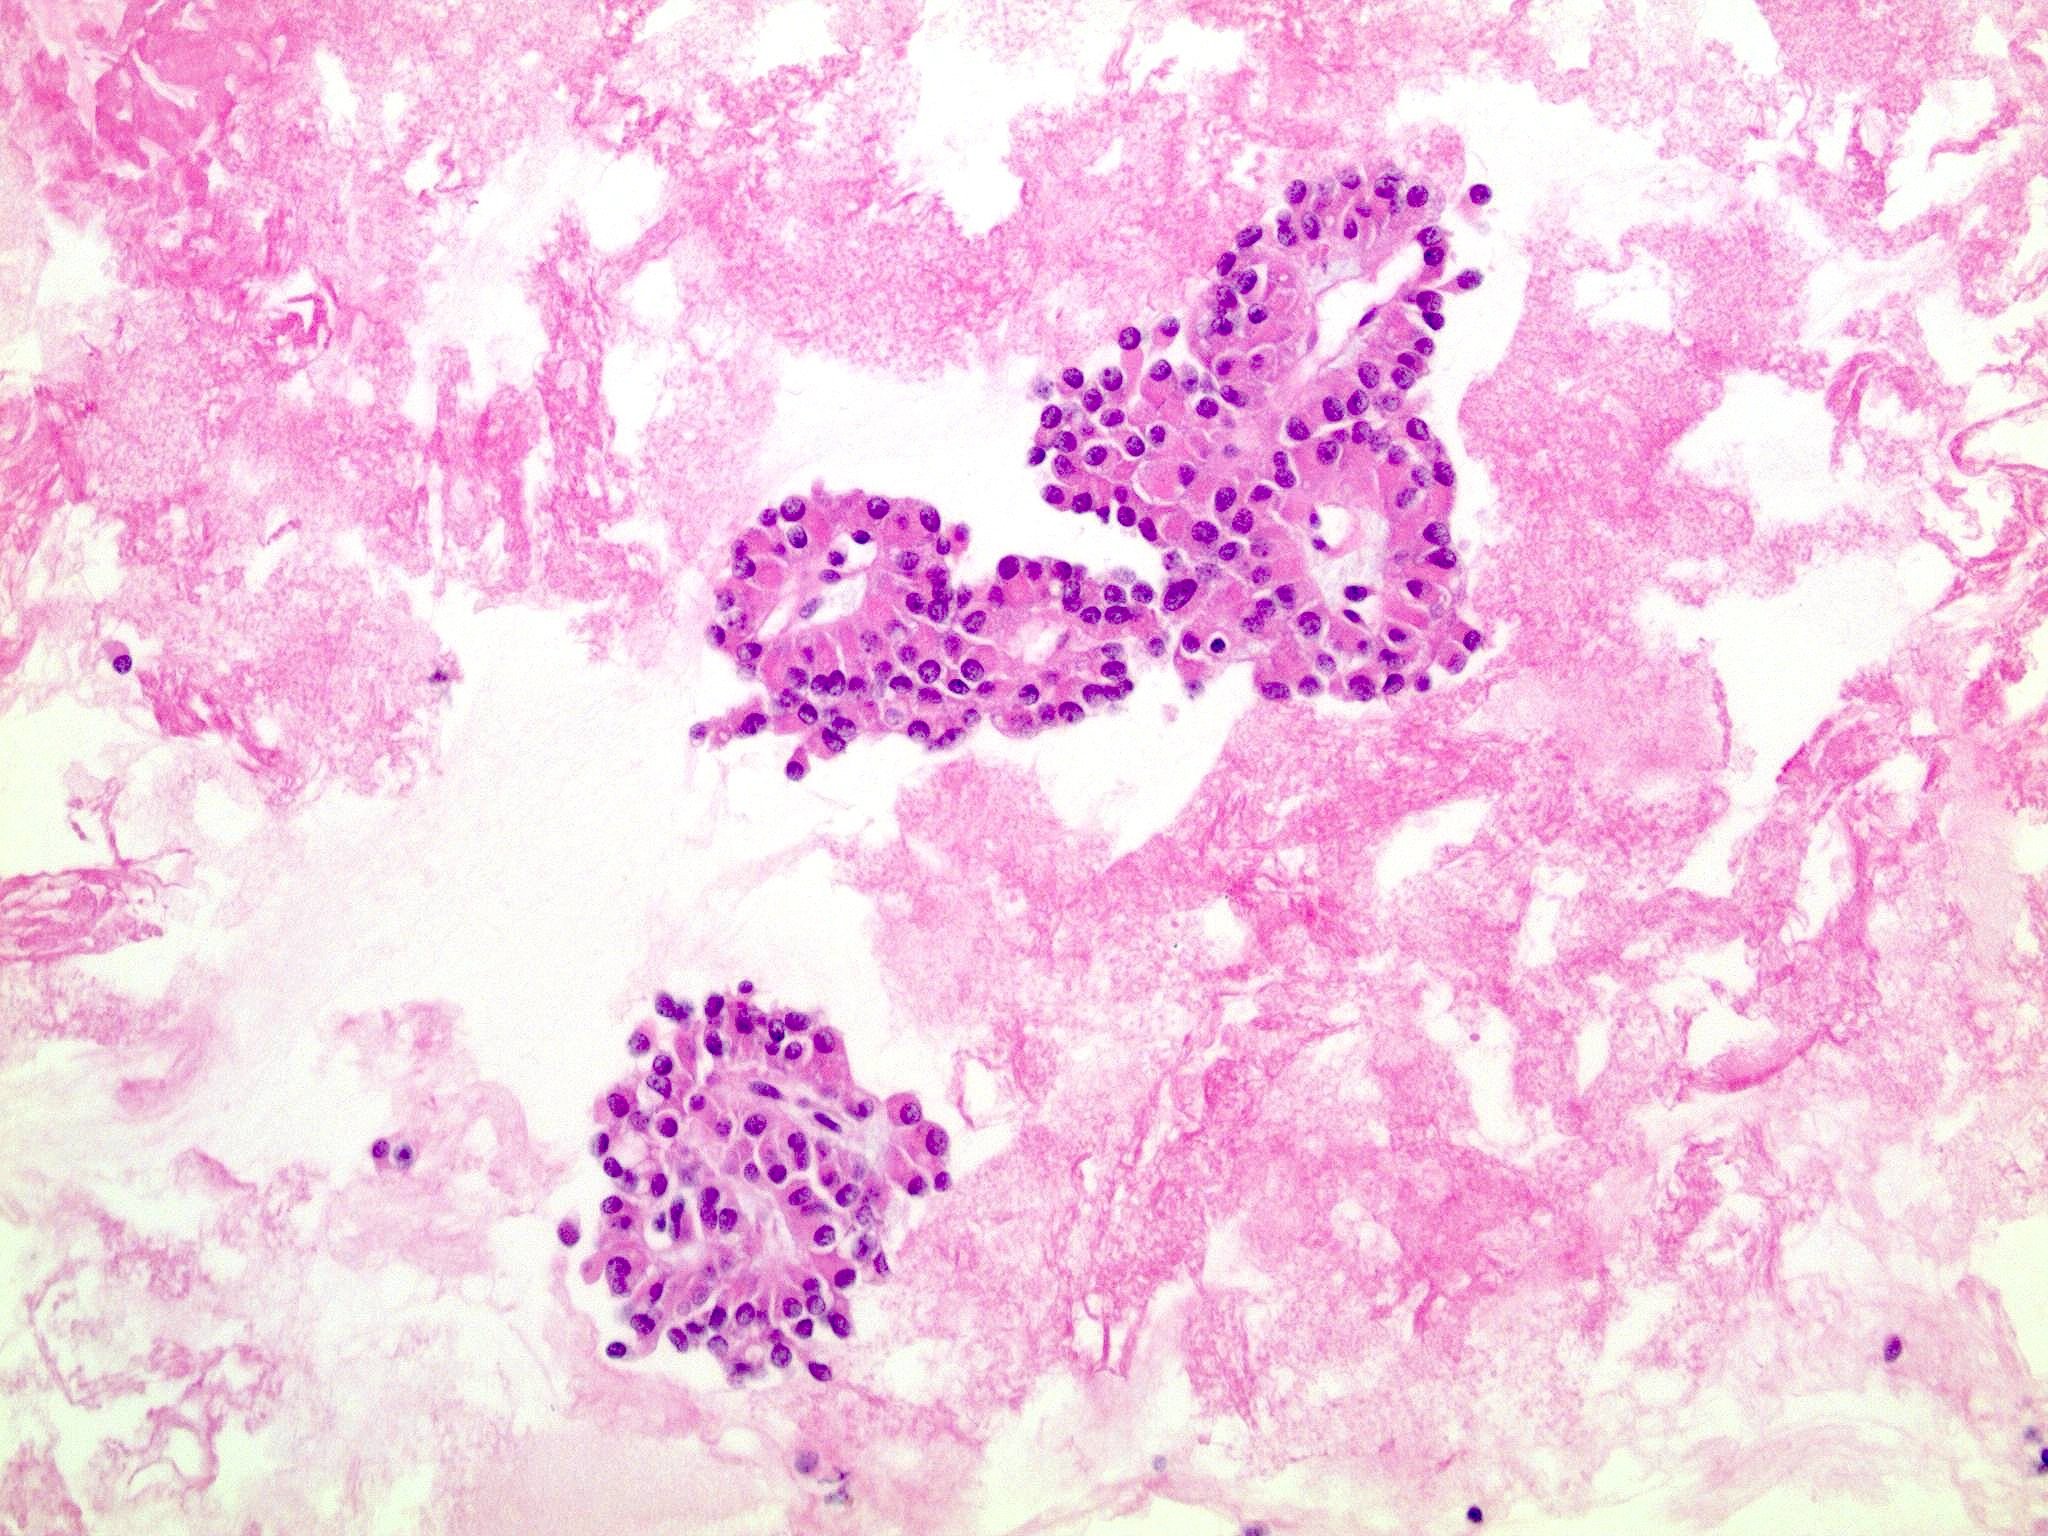

Microscopic (histologic) description

- Tumors are heterogeneous, with variable admixture of solid and pseudopapillary areas

- Solid areas are comprised of uniform cells admixed with capillary sized blood vessels

- Pseudopapillae are formed due to tumor cells getting detached from blood vessels forming fibrovascular stalks or rosette-like structures (Arch Pathol Lab Med 2020;144:829)

- Stroma usually shows various degrees of hyalinization or evidence of degeneration, such as hemorrhage, foamy macrophages, calcification and cholesterol clefts

- Tumor cells usually have a moderate amount of eosinophilic cytoplasm with intracytoplasmic hyaline globules (PAS+ and diastase resistant, positive for alpha-1-antitrypsin) and perinuclear vacuoles (Am J Surg Pathol 2011;35:981)

- Relatively uniform nuclei with finely textured chromatin, inconspicuous nucleoli and characteristic longitudinal grooves

- Variants include clear cell, oncocytic and pleomorphic

- Rare mitotic figures

- Although grossly well circumscribed, microscopic finding of infiltration to the surrounding pancreatic tissue is not uncommon

- Rare cases of highly aggressive behavior; histological features in those cases included diffuse growth pattern, extensive necrosis, significant nuclear atypia, high mitotic count (35 - 70/50 high power fields) or sarcomatoid features (Am J Surg Pathol 2005;29:512)

Microscopic (histologic) images

Contributed by Monika Vyas, M.D., Omid Savari, M.D. and Raul S. Gonzalez, M.D.